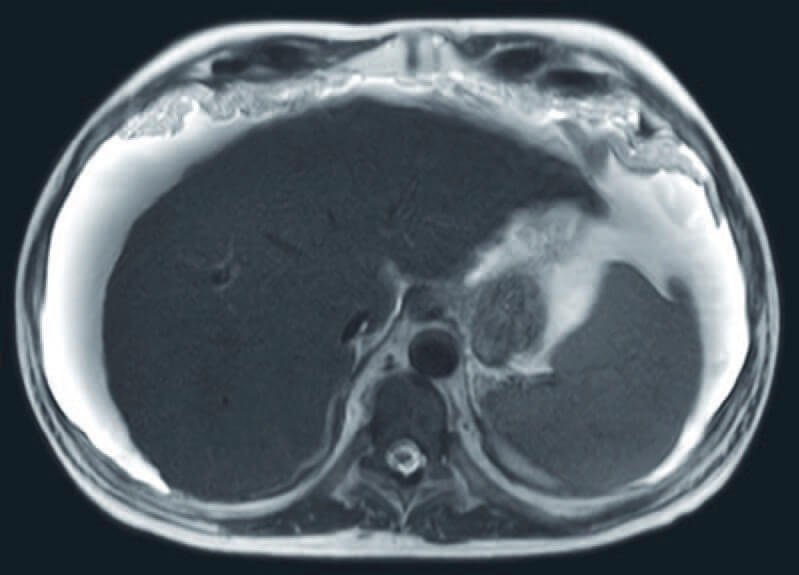

Body